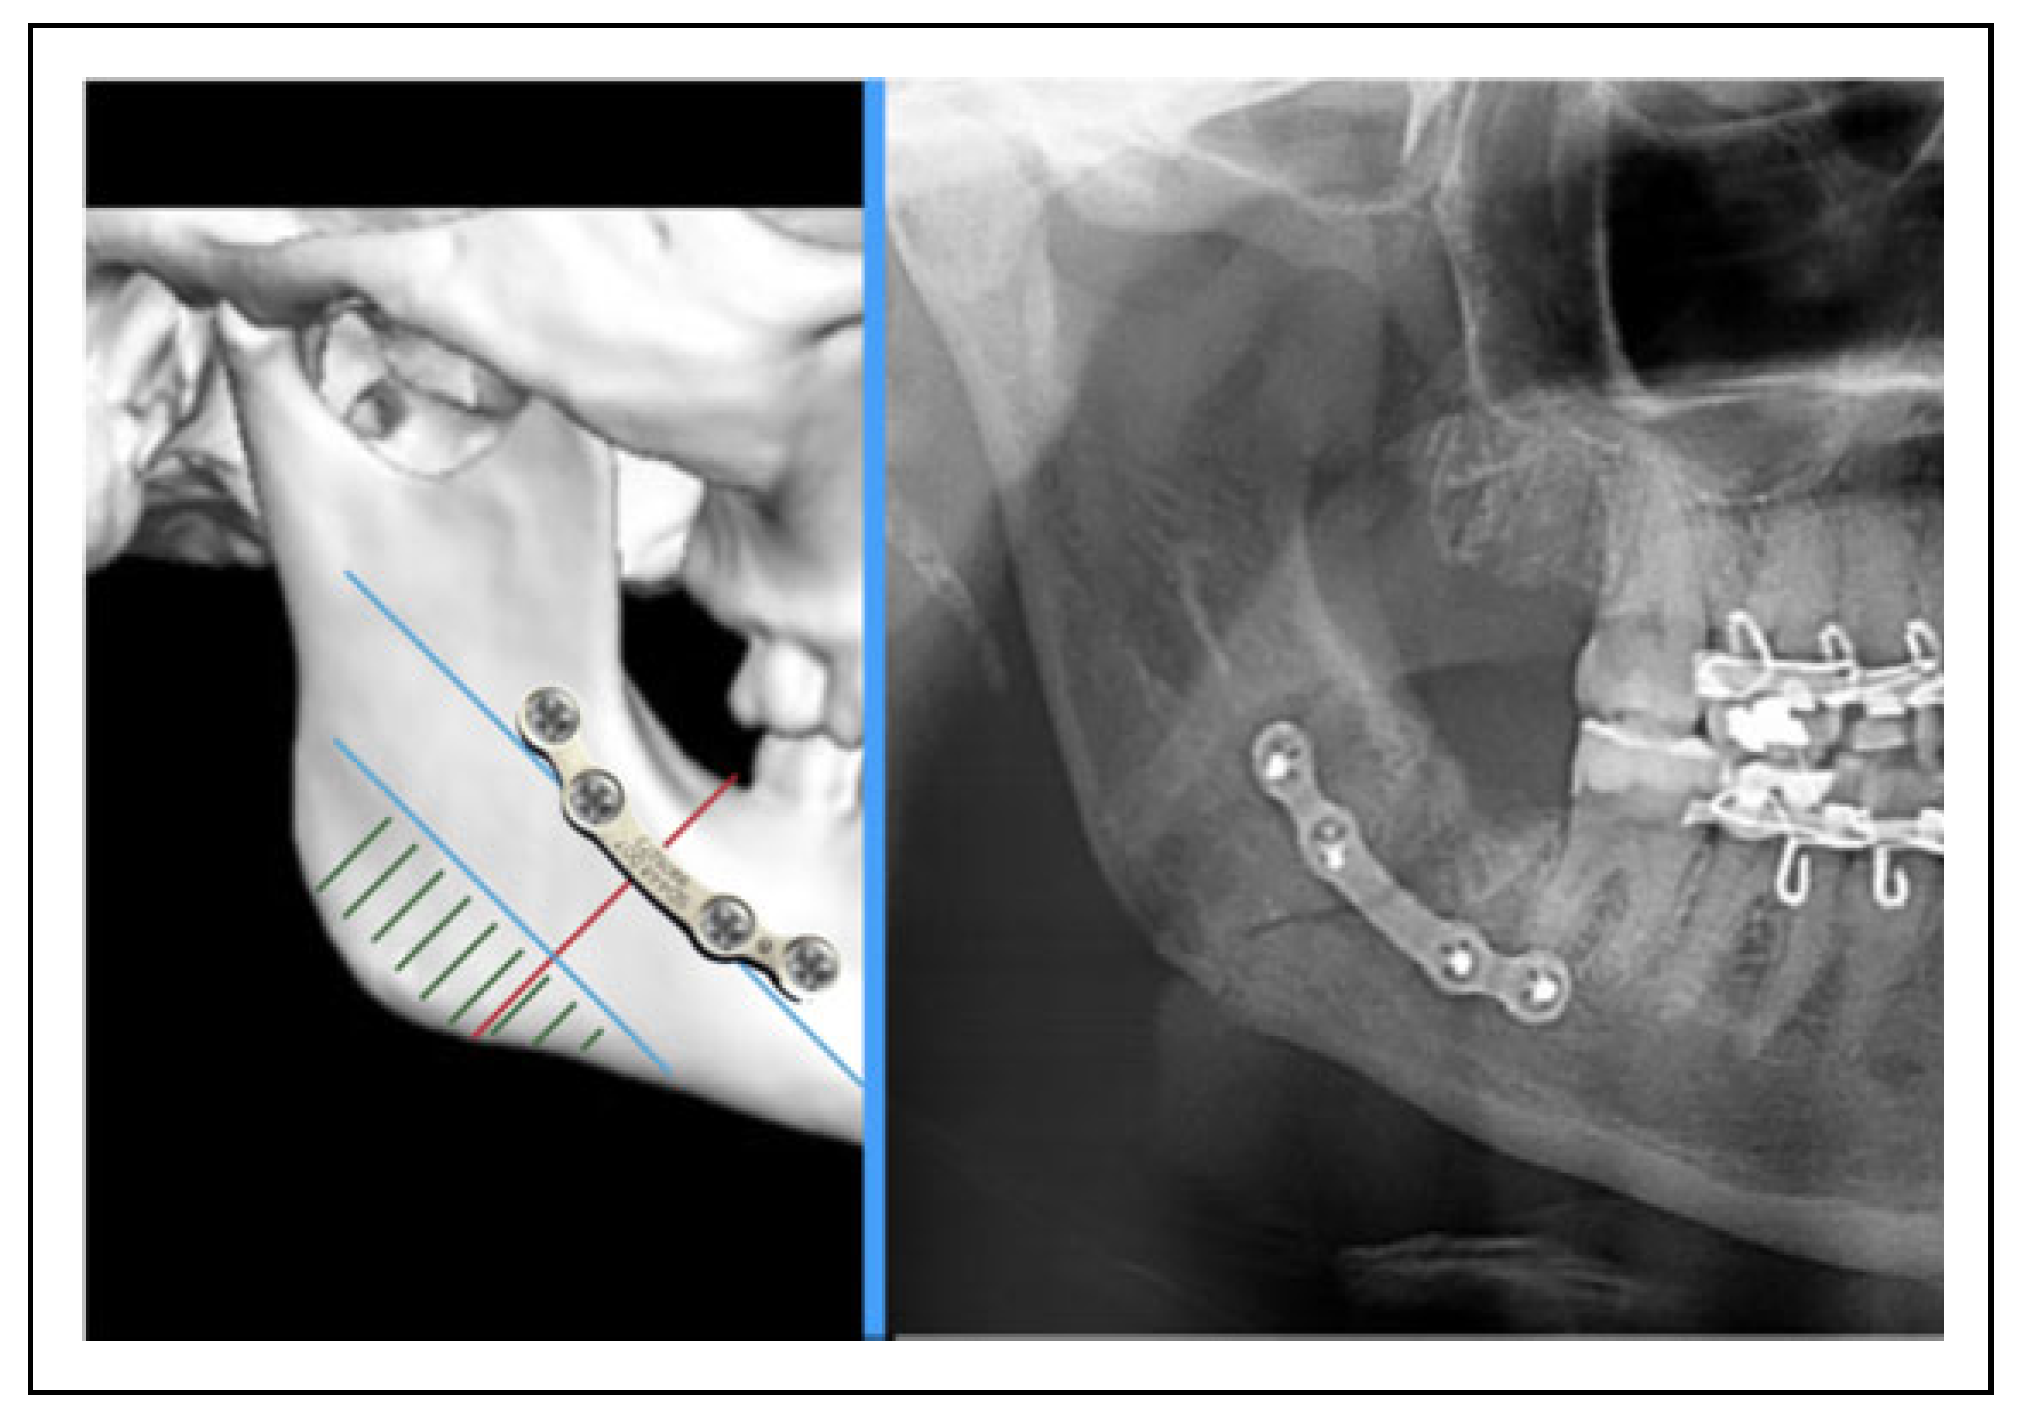

Is There a Safe Zone for Lateral Border Fixation of Mandibular Angle Fractures?

2. Methods

3. Results

4. Discussion